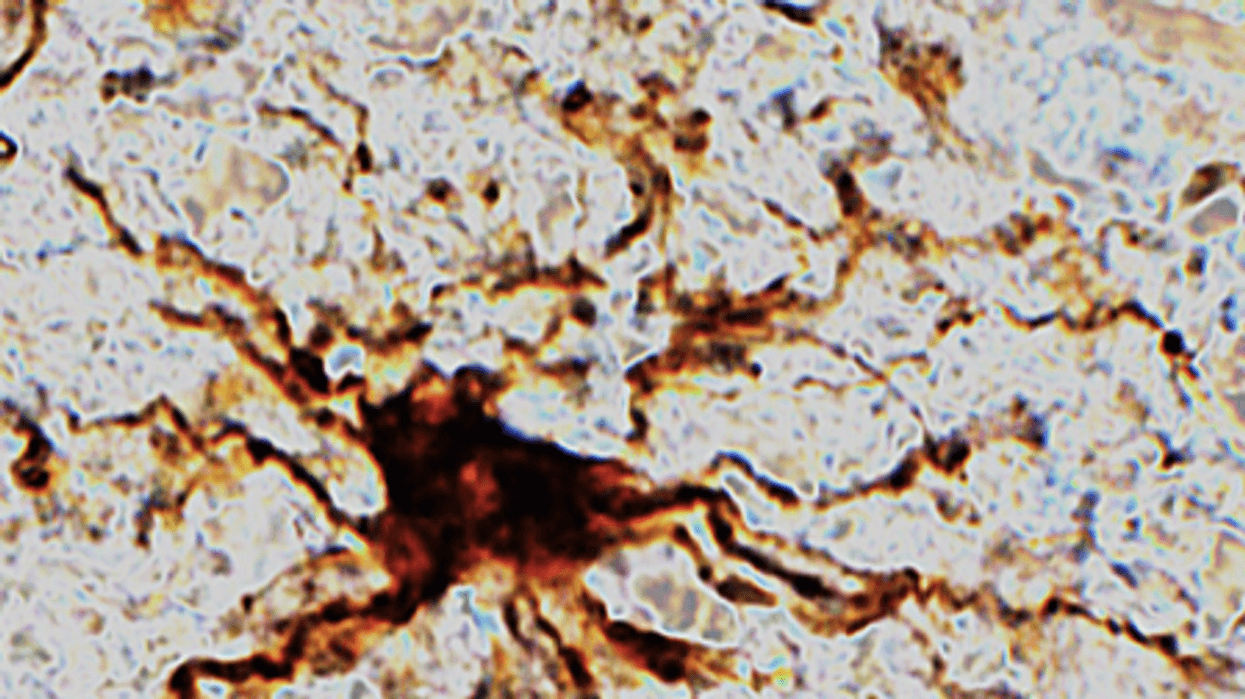

The growing genes were specific to a certain type of brain cell — inflammatory cells called glial cells. They sprout armlike appendages for several hours after death.

“That glial cells enlarge after death isn’t too surprising given that they are inflammatory and their job is to clean things up after brain injuries like oxygen deprivation or stroke,” said Dr. Jeffrey Loeb, head of neurology and rehabilitation at the UIC College of Medicine.